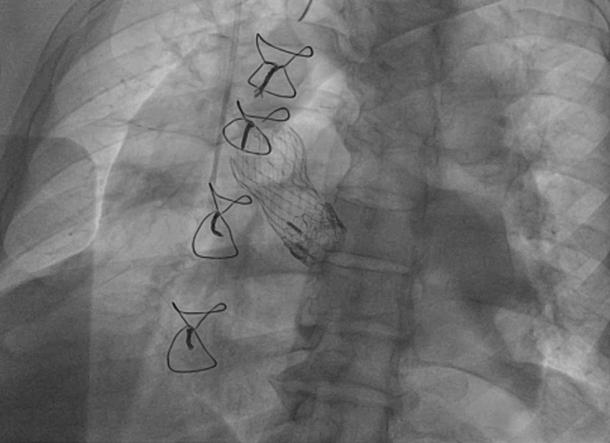

Transcatheter aortic valve replacement within a degenerated surgical bioprosthetic aortic valve is increasing in frequency. We present a rare case of a patient requiring a second TAVR placed within a previous placed degenerated transcatheter aortic valve, which was implanted in a degenerated surgical bioprosthetic aortic valve. ().

在退化的外科生物人工主动脉瓣内行经导管主动脉瓣置换术的频率正在增加。我们报告了一例罕见病例,一名患者需要在先前植入的退化经导管主动脉瓣内行第二次经导管主动脉瓣置换术,而该经导管主动脉瓣是植入在退化的外科生物人工主动脉瓣内的。()